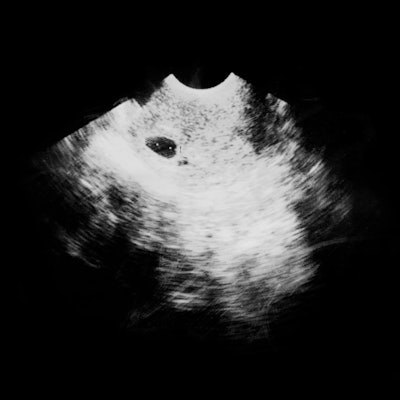

Mehr als den Gang zur Toilette hatte der Arzt der 38-Jährigen nicht erlaubt, nachdem im Ultraschall ein zu kurzer Gebärmutterhals aufgefallen war – ein bekanntes Warnzeichen für eine Frühgeburt. Als der Sohn schließlich in der 32. Woche zur Welt kam, war die Mutter so schwach, dass sie mit dem Rollstuhl zum Neugeborenen geschoben werden musste.

Der wichtigste Durchbruch der letzten Zeit ist Surbek zufolge aber der Einsatz von Progesteron gewesen. Das Geschlechtshormon beruhigt die Muskulatur der Gebärmutter und des Uterus. Ohne Progesteron, das weiß man schon lange, kommt es zum Abbruch der Schwangerschaft. Inzwischen hat sich herausgestellt, dass das Hormon das Risiko einer Frühgeburt um 40 bis 60 Prozent verringern kann, wenn bei der Ultraschalluntersuchung eine Verkürzung des Gebärmutterhalses auffällt.